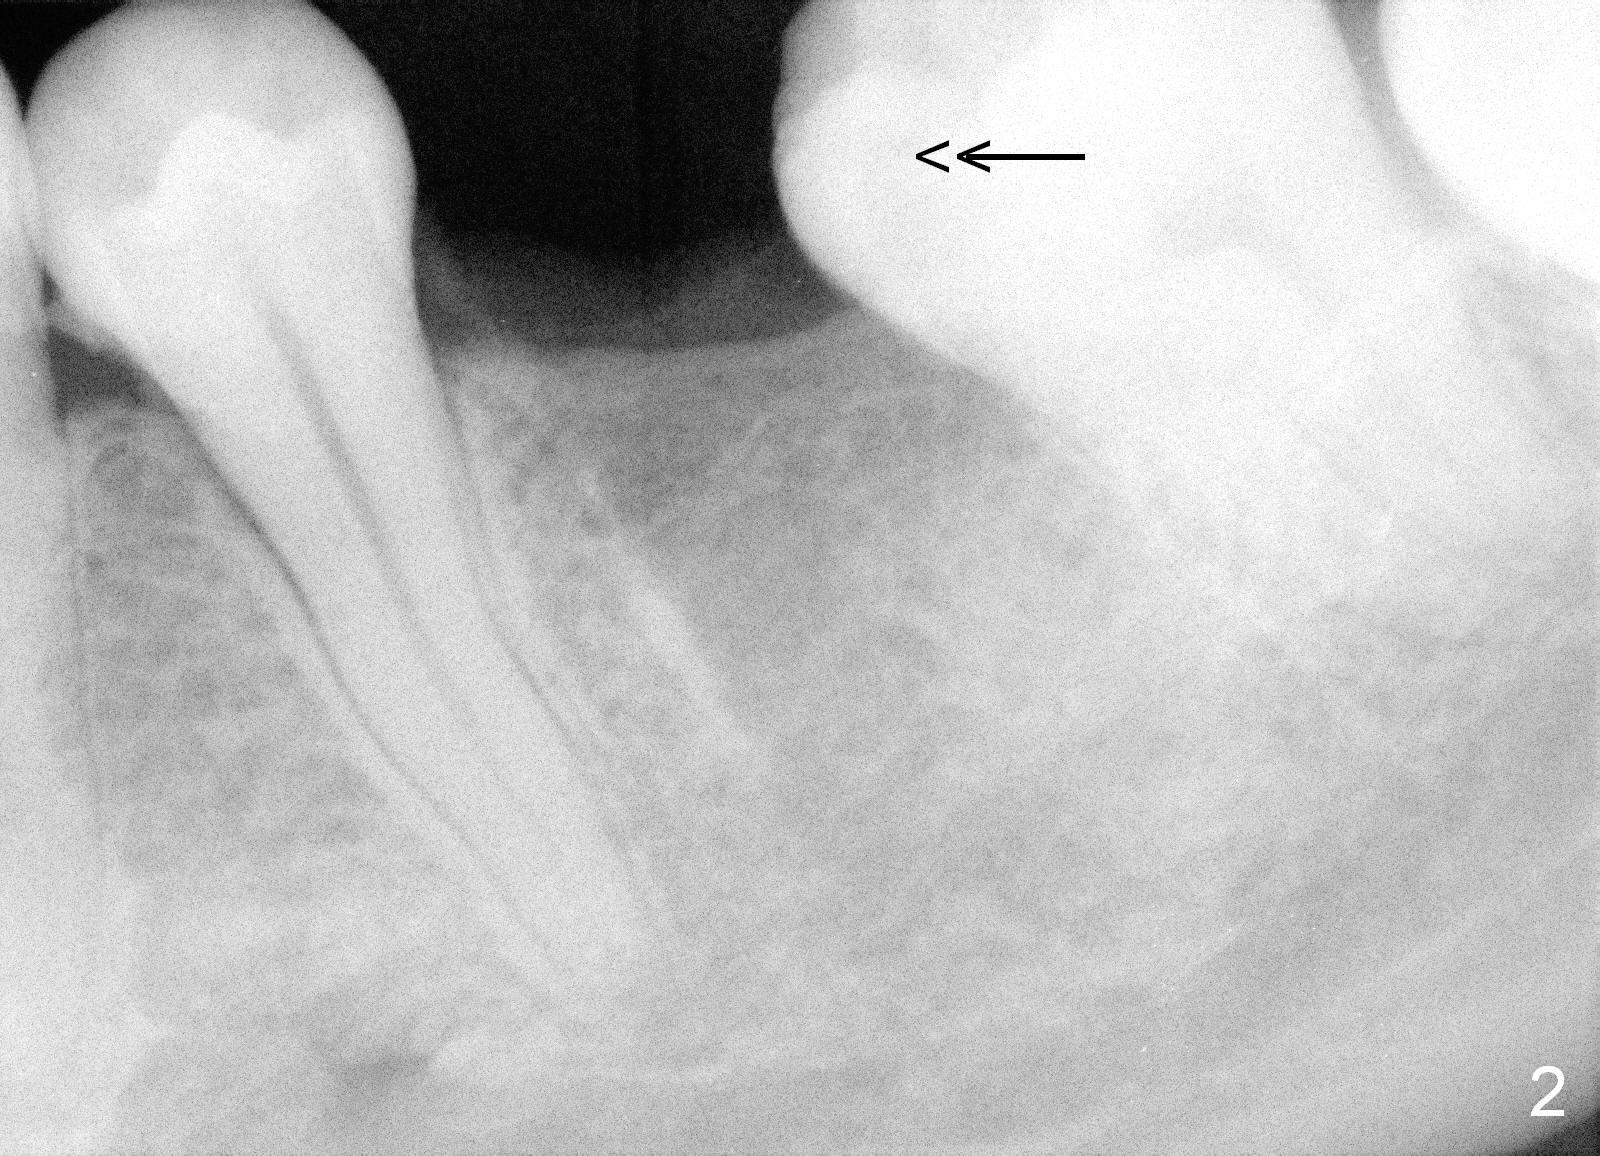

A 29-year-old man presented for #19 extraction a year ago (Fig.1). Probably due to long-termed loss of the distal portion of the crown of #19 (*), the tooth #18 has undergone mesial tilting (arrow). Now he returns requesting implant, but the tilting is worse (Fig.2 double arrows). What X-ray cannot show is severe atrophy buccolingually, increasing difficulty in implant placement. A much smaller implant can be placed (Fig.3), as compared to an immediate implant.

Reamers are used for osteotomy and saving the autogenous bone with control of depth. Bone graft is most likely placed buccodistally (Fig.3 red circle). To prepare the recipient site (decortication), surgical handpiece is needed. Long-termed resorption membrane is cut to cover the graft.